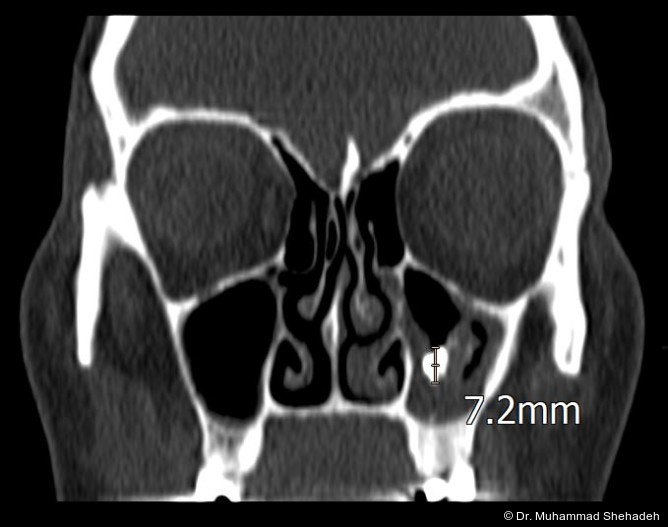

Eine 40-jährige Patientin wurde von ihrem HNO-Arzt in unsere Praxis für Mund-, Kiefer- und Gesichts­chirurgie überwiesen. Die Überweisung erfolgte aufgrund eines in der Computertomografie (CT) ­nach­gewiesenen, röntgendichten Fremdkörpers in der linken Kieferhöhle.

Die Läsion wies eine Größe von etwa 7 mm auf. Klinisch klagte die Patientin über ein anhaltendes Druckgefühl im linken Mittelgesicht sowie über wieder­kehrende, als „Erkältung“ wahrgenommene Beschwerden, entsprechend einer ­chronischen Sinusitis mit rezidivierenden akuten Schüben.